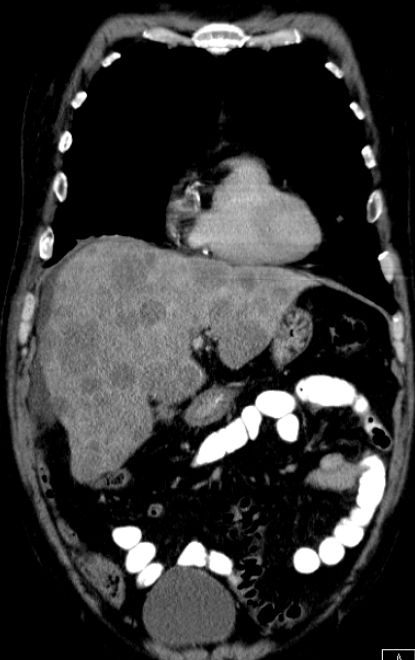

RCh mit Mitomycin-FU Lebermetastasen bei Plattenepithel - Ca des Anus